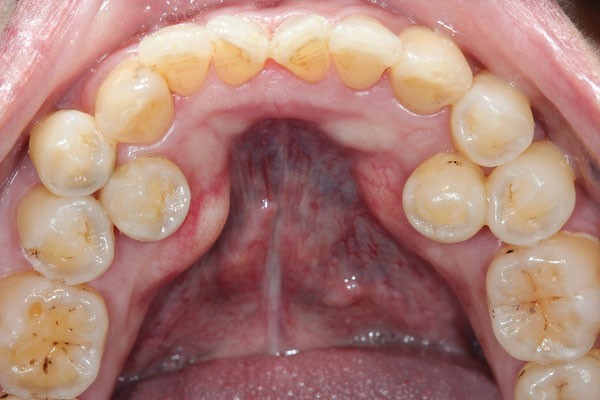

To explore these questions, Owaise Sharif and co-authors carried out a service evaluation of the joint dento-alveolar (JDA) clinic at the Croydon University Hospital. A prospective patient note analysis was carried out of 100 new patients attending between November 2014 and September 2015. Fifty-four percent of the patients were female, with the mean age 17 years. The most common anomalies referred were:

Impacted canines (49%)

Supernumeraries (16%)

Impacted second premolars (10%).

In addition to the service analysis described in part 1 of the BDJ series, in part 2 the authors provide an overview of common dental anomalies. Their definition, classification, aetiology and prevalence have been outlined along with their diagnosis and management. The aim of this is to increase awareness amongst practitioner's and help them formulate appropriate treatment plans. Part 1 of the series covers soft tissue anomalies, dentigerous cysts, transpositions and supernumerary teeth. Whereas part 2 focuses on impacted teeth, delayed and failed eruption, ankylosed incisors and infra-occluded deciduous molars.

Dental anomalies are often asymptomatic and may develop from an early age, the GDP therefore has a crucial role in early identification and management. In addition, dental anomalies often require onward referral to a specialist for management and so knowledge of potential management strategies will aid the GDP in counselling patients.